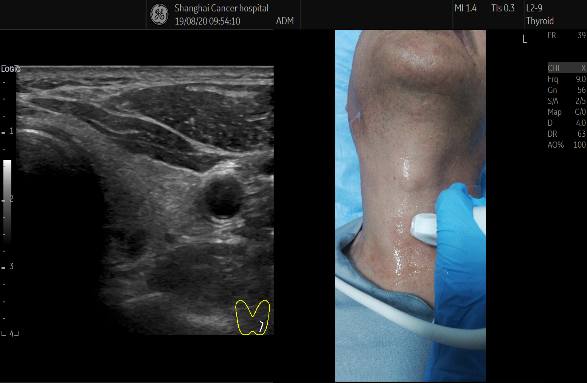

三、美國(guó)GE LOGIQ E11 彩超

美國(guó)GE LOGIQ E11 彩超 的全新技術(shù)

1.全模态彈性成像技術(shù)

應力式彈性成像和複合剪切波彈性可(kě)應用于腹部、淺表、婦科、泌尿、兒科等領域,對于慢(màn)性病的評估、腫瘤良惡性鑒别、癌前病變的早期判定、損傷評估等疾病有重要的臨床意義。

4. 在超聲介入領域

B-Steer+穿刺針增強技術(shù):清晰呈現穿刺及治療路(lù)徑,提高進針成功率及操作(zuò)信心。

聲影(yǐng)同屏技術(shù):穿刺及消融時将病人(rén)體(tǐ)位,探頭位置,進針部位與超聲圖像同屏顯示。